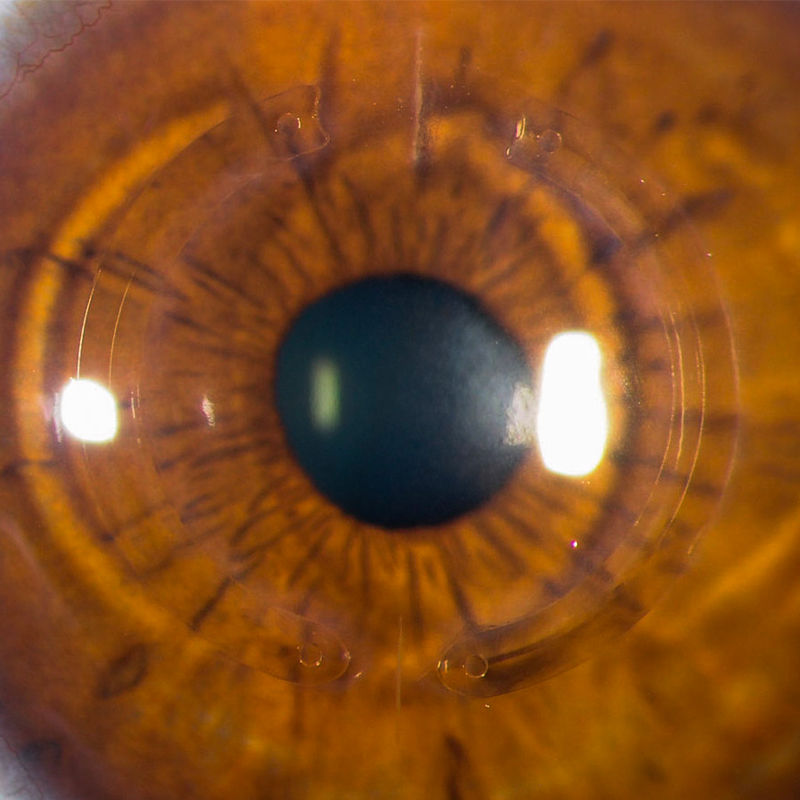

Anillos Intraestromales

Los anillos intraestromales reducen la irregularidad de la córnea, mejoran el astigmatismo y la miopía y nos permiten evitar o retrasar la necesidad de un trasplante de la córnea. El tratamiento con anillos puede complementarse con crosslinking y con gafas o lentes de contacto para mejorar la visión.